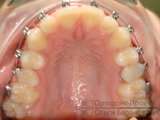

Брекет-система Damon на зубах (стрелочками показан несъемный ортотик):

Для постановки в ряд зуба, который растет внутри, установлена специальная пружина, раздвигающая соседние зубы для создания необходимого пространства и возвращающая верхний зубной центр на место.

На фотографиях видно, что 15-й зуб встал в зубной ряд.

На 1-ом этапе коррекции ортодонта выполнено следующее:

- создано место для 15-го зуба;

- выровнены все зубы, включая постановку в зубной ряд 15-го;

- нормализована форма зубных рядов.